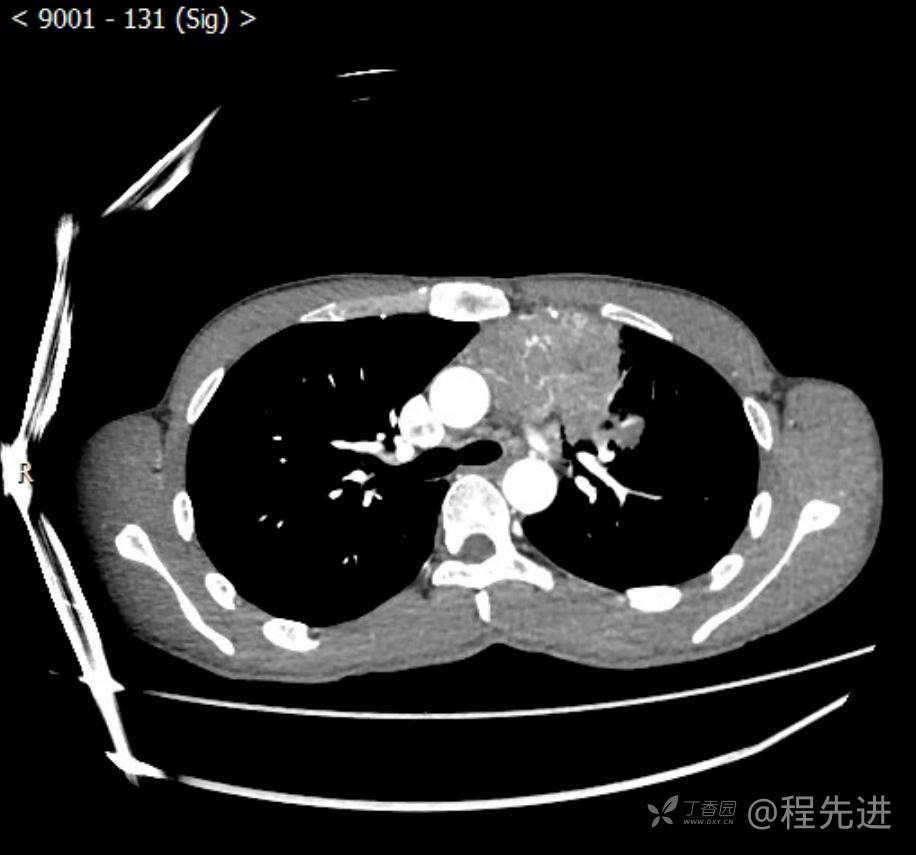

主诉:反复咳嗽1月,发现“纵隔”占位半月,乏力10余天。

现病史:患者1月前无明显诱因出现咳嗽,以夜间为著,伴有少量白痰,无发热,无胸痛、咯血,无痰中带血,未予重视,半月前外院行胸部CT检查发现“左前上纵隔”占位,未予进一步检查及治疗。近10余天自觉乏力,逐渐加重。